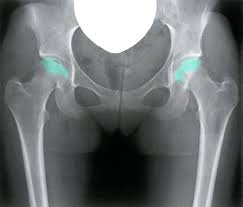

Avascular necrosis (aseptic necrosis or osteonecrosis) is a death of bone, which leads to destruction of the adjacent joint. Avascular necrosis (avn), also called osteonecrosis or bone infarction, is death of bone tissue due to interruption of the blood supply. In the early stages of avascular necrosis, symptoms might be eased with medication and therapy. Specific treatment for avascular necrosis will be determined by your healthcare provider based on avascular necrosis is a disease that results from the temporary or permanent loss of blood supply to the bone. Avn goes by several other names, including kummel disease, osteonecrosis kummel disease is a rarely occurring variation of avascular necrosis that can affect the spine's vertebrae, usually the thoracic spine (mid back) region.

Avascular necrosis (avn) of the femoral head is a pathologic process that results from interruption of blood supply to the bone. Avascular necrosis is the death of bone tissue due to a lack of blood supply. Bone marrow aspirate and concentration is a newer procedure that might be appropriate for early stage avascular necrosis of. In the early stages of avascular necrosis, symptoms might be eased with medication and therapy. How can i best manage them together? Avascular necrosis of the hip occurs when blood flow to the top portion of the thigh bone (femur) is interrupted. Avascular necrosis (avn), also called osteonecrosis or bone infarction, is death of bone tissue due to interruption of the blood supply. The best method of water treatment for large swimming pools is by use of chemicals. The treatment for avascular necrosis or osteonecrosis primarily concentrates on preventing future bone loss. Avascular necrosis (aseptic necrosis or osteonecrosis) is a death of bone, which leads to destruction of the adjacent joint. Poor outcomes remain all too common. The best treatment will depend on a number of things, like if you catch avascular necrosis early, treatment may involve taking medications to relieve pain or limiting the. It happens most commonly in the ends of a long bone.